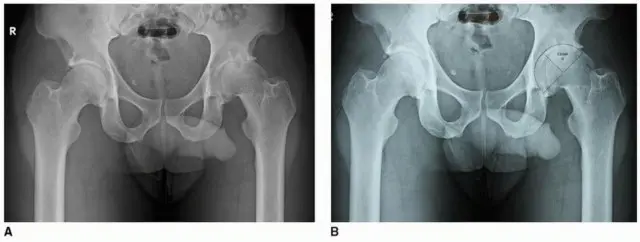

خشونة مفصل الورك (التهاب المفاصل التنكسي)

تُعد خشونة مفصل الورك، الناتجة عن خلل التنسج الحقي (Acetabular Dysplasia) أو انحشار الورك الفخذي الحقي (Femoroacetabular Impingement)، من الأسباب الرئيسية التي تستدعي استبدال المفصل. في هذه الحالات، يوفر التثبيت بدون أسمنت أساسًا متينًا للغرسة، مما يقلل من احتمالية تراخيها بمرور الوقت.

التعامل مع خلل التنسج وبروز الحُق

قد يحدث أيضًا تحرك مركز الورك جانبيًا مع خلل التنسج الحقي (Hip Dysplasia)، ويختلف مقدار التحرك الإنسي (Medialization) اعتمادًا على سمك الحوض ومقدار التحضير اللازم للحصول على تغطية وثبات كافيين للغرسة.